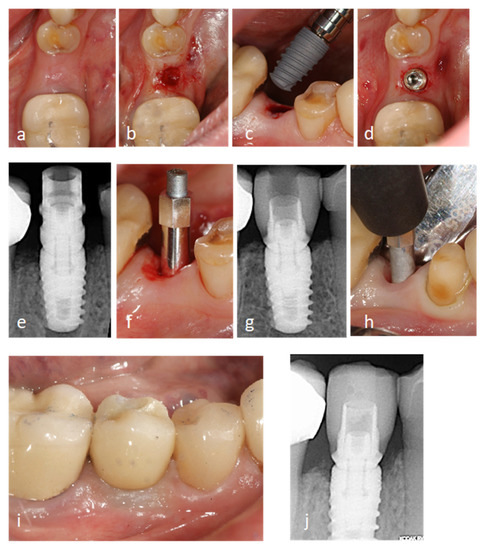

Jcm Free Full Text A Randomized Clinical Trial Comparing Immediate Loading And Delayed Loading Of Single Tooth Implants 5 Year Results Html